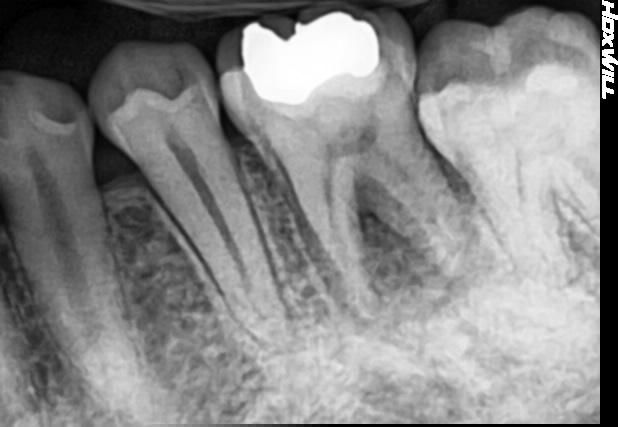

4번째 사진은 치료가 끝나고 6주 뒤의 사진입니다.

다만 걱정이 되는건 3에서 4번째 사진으로 넘어갈때 치아 중앙부 중간부분(가운데 큰 약재 바로 밑부분)에 색깔이 좀 달라보입니다. 혹시 치아 금은 아니겠죠?

• 4번 째 사진

사진상으로 보면 치아 뿌리끝 염증이 없어지는 양상을 띄는거 같습니다. 잘 치료 된거 같으니 너무 걱정하지마세요.

해당부위의 투과상은 엑스레이 찍는 각도에 따라서 다르게 보이기도 하는 부분입니다.

더 눈여겨봐야할 부분은 치아 뿌리 부위의 투과상인데 3->4에서 치아 뿌리 부위 염증이 다소 개선되고 있는 부분이 관찰됩니다. 좀 더 증상은 지켜보면 좋을 것 같습니다.